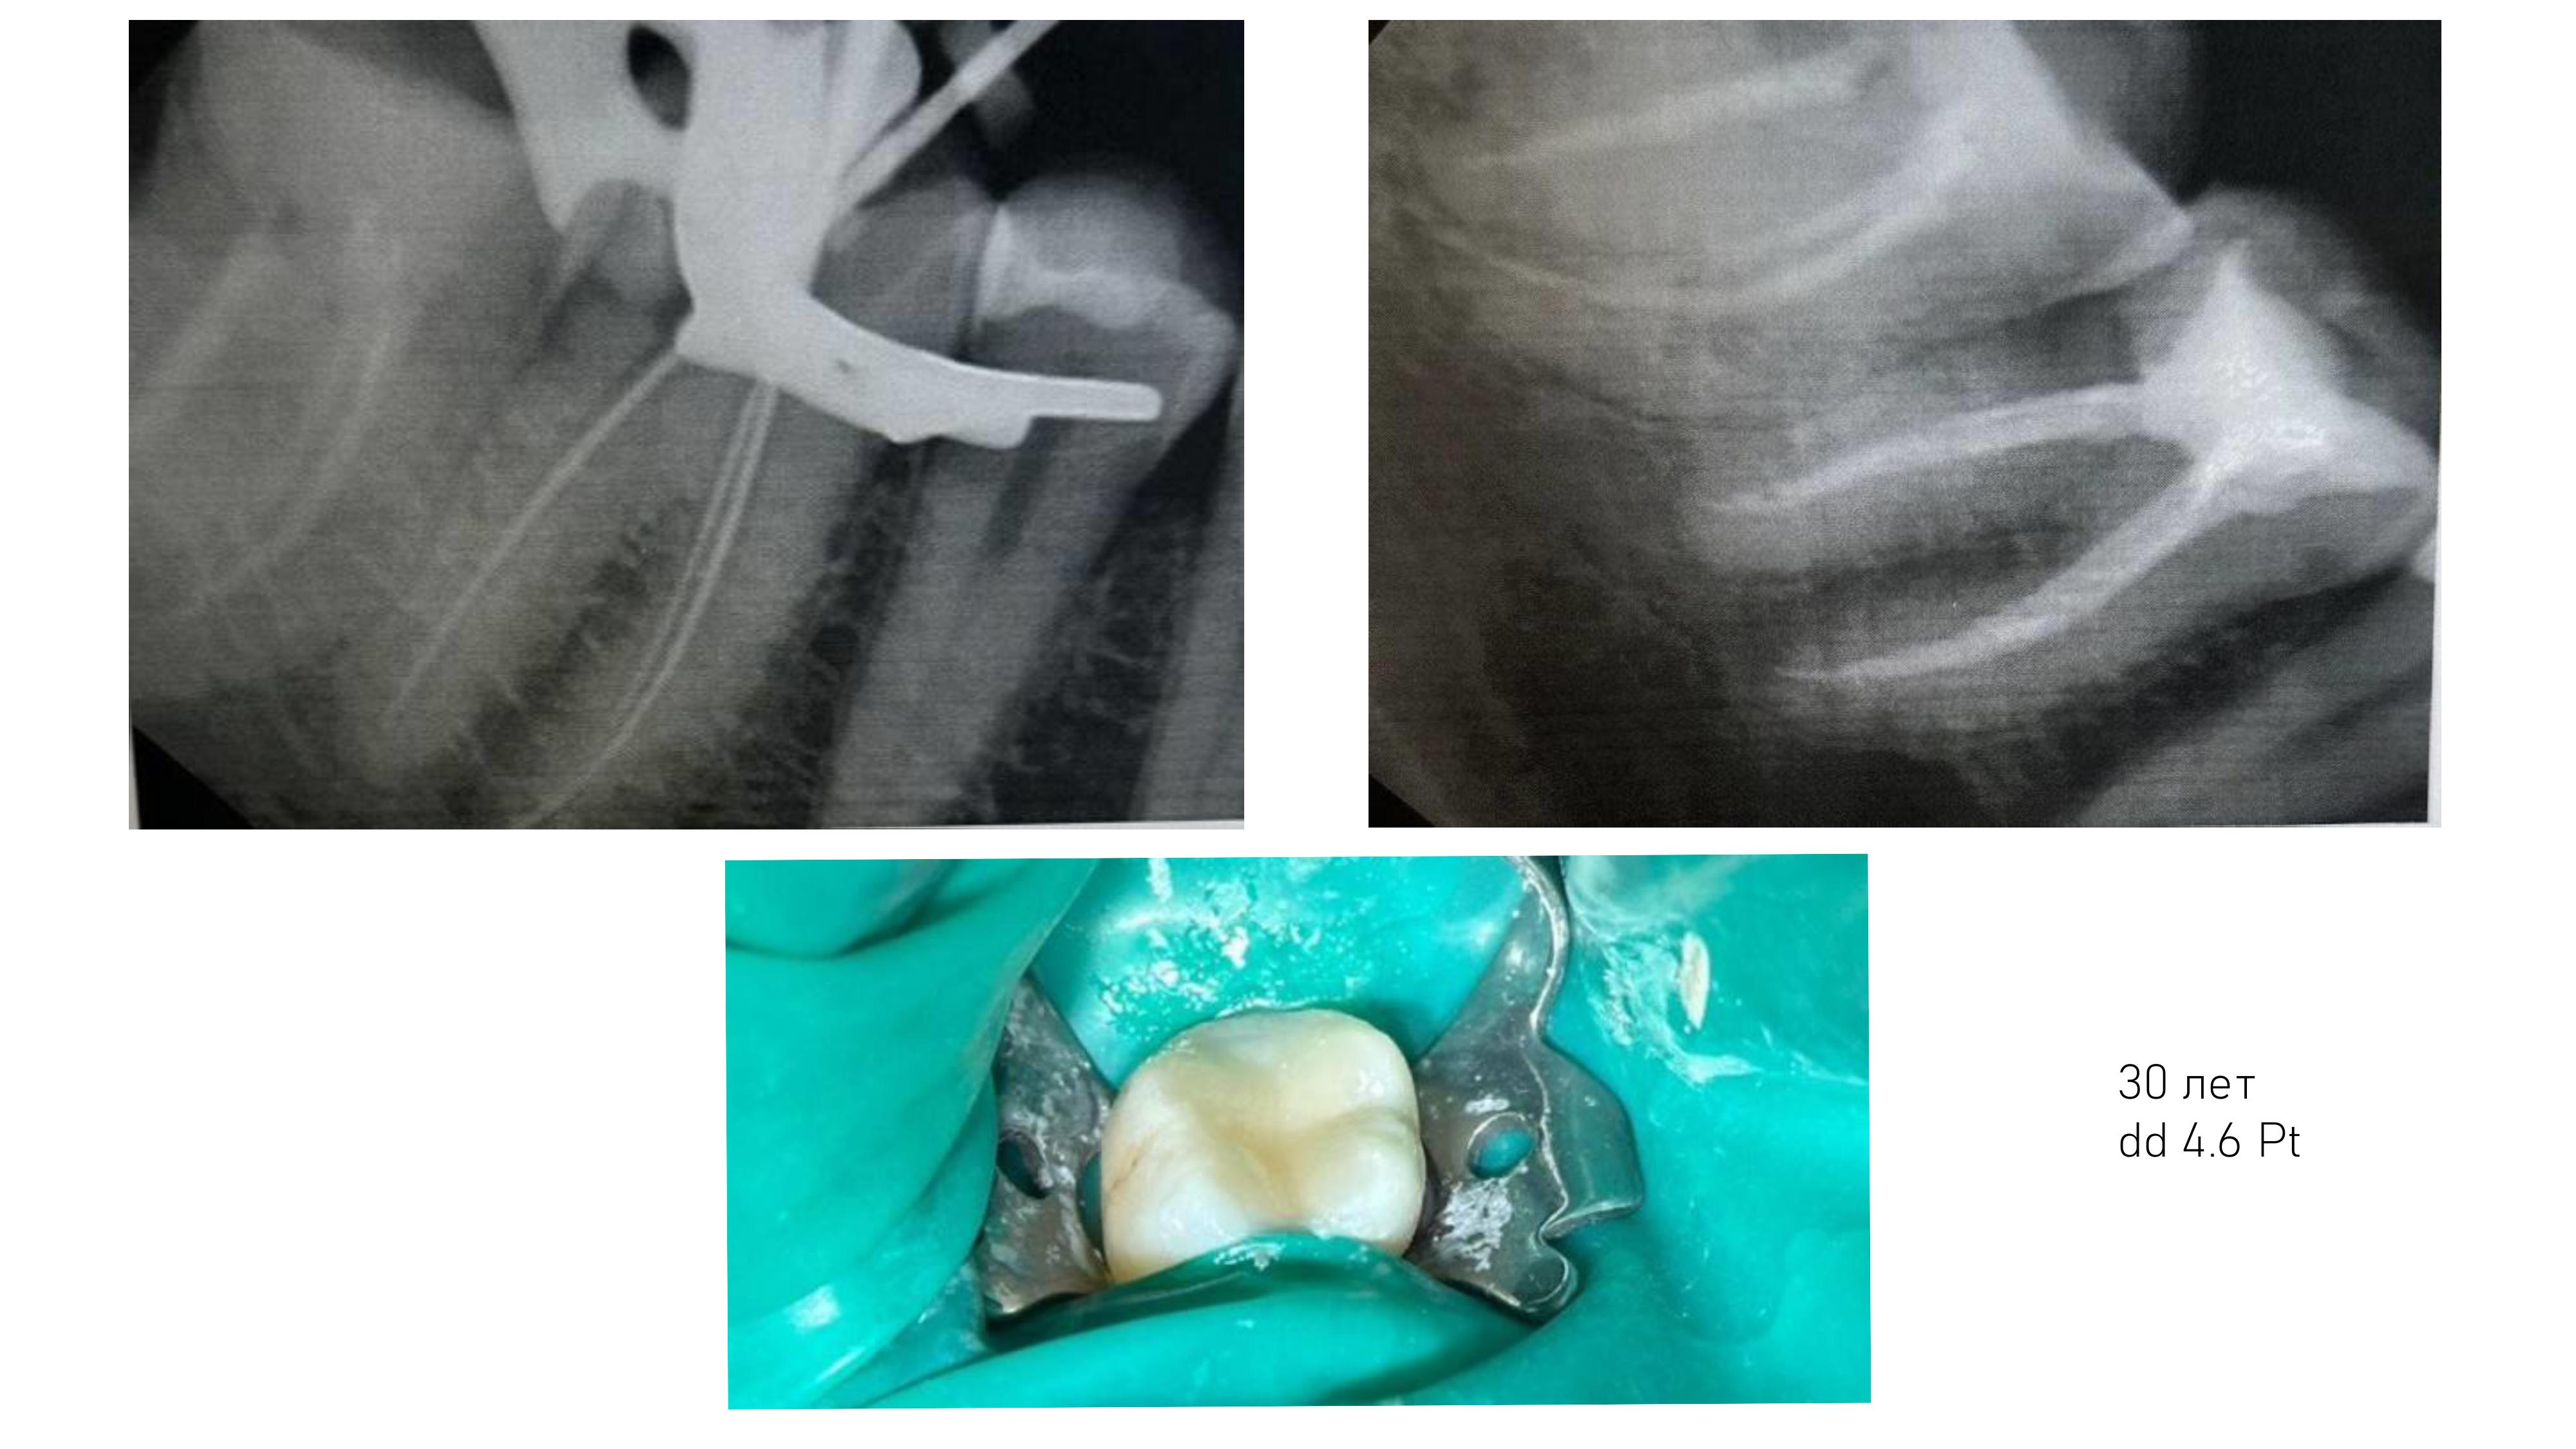

6. Диагностика и лечение кариеса временных и постоянных зубов с использованием микроскопа, лечение пульпитов и периодонтитов временных и постоянных зубов.

7. Подготовка зубов к ортопедическому и ортодонтическому лечению, с учетом назначенного плана лечения